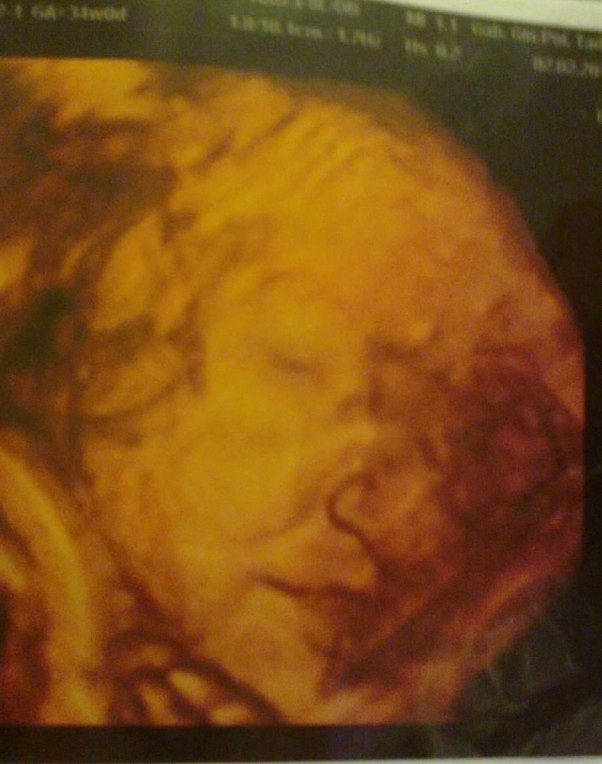

Byłem z Paulą na badaniu usg. Jestem w szoku że tam wszystko tak widać jak się rusza i uśmiecha. Teraz to już się doczekać nie mogę kiedy junior się urodzi. Moja Paula to się aż rozpłakała. Kochana.